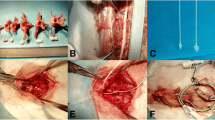

Dogs were allocated to four groups. Group A (control) underwent laminectomy of T7 without shortening the spinal column. Groups B, C and D had 1/3, 1/2, and 2/3 of T7 resected, respectively, followed by spinal shortening. Somatosensory evoked potential (SSEP) and hind-limb function were recorded periodically for 14 days after operation. Spinal cord blood flow (SCBF) and BSCB were detected at the acute phase of shortening. Microglia/macrophage reactions and iNOS activity were observed by immunohistochemistry.

Shortening of 1/3 of a vertebral height caused no significant changes in SSEP and hind-limb function after operation, whereas shortening of 1/2 of the height caused SSEP abnormality and paraparesis, and severe neurologic deficit of hind-limb was observed when the shortening reached 2/3 of the height. SCBF increased temporarily and showed a trend of recovery when the shortening was within 1/2 of a vertebral segment height. When it reached 1/2 or 2/3 of the height, SCBF at 6 h post-operation was 86.33% or 74.95% of the baseline, and an increasing BSCB permeability was observed. In the subsequent 7 days, obvious activation of macrophage and increased number of iNOS-positive cells were observed.

It is safe to shorten the spinal cord within 1/3 of a vertebral height in middle thoracic spine under two-segment laminectomy in canine. The BSCB disruption, macrophage activation, and increased iNOS activity were observed in the acute phase of the injury.

All authors contributed to the study conception and design. The animal models were performed by Le Ji, Wenchen Ji, Binshang Lan and Lisong Heng. SSEP monitoring was performed by Yajuan Huang and Min Feng. Material preparation, data collection and analysis were performed by Xiaoying Ma, Shengli Huang and Jingyuan Li. The first draft of the manuscript was written by Le Ji and all authors commented on previous versions of the manuscript. All authors read and approved the final manuscript.